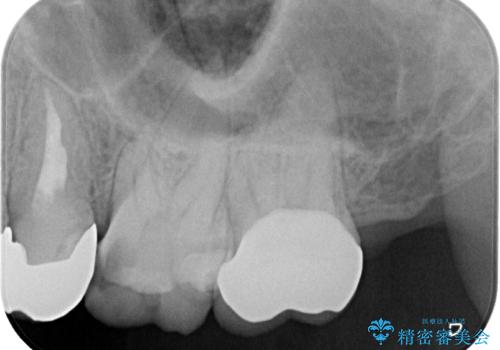

- メインテナンス時に詰め物が外れているのでやり替えたいとのことで来院された患者様です。

以前にも詰め物が外れてオールセラミッククラウンによる補綴治療を行っており、今回も詰め物の範囲が大きい為オールセラミッククラウンによる被せもの治療を行うことになりました。

拡大鏡視野下でコンポジットレジン、虫歯を除去しオールセラミッククラウンに適した形に整えました。